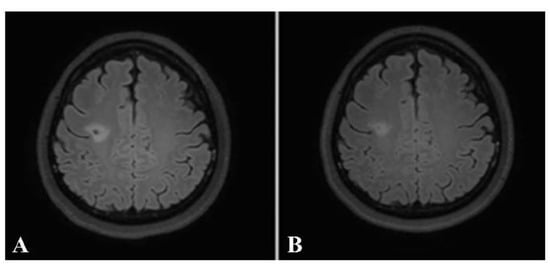

A brain MRI was available for all 32 patients, all of whom showed abnormalities. Most of the patients (19, 59.4%) were subjected to MRI soon after clinical presentation and during follow-up. The lesions were most commonly identified in the periventricular regions (78.1%), juxtacortical regions (75%) and deep white matter (62.5%). Cortical lesions were identified in only eight patients (25%). Other locations included in the McDonald criteria (2017) were the brainstem and cerebellum, which were found in 59.4 and 21.9% of all patients, respectively. The most common characteristic of the lesions was a round/oval discrete appearance (29 patients, 90.6%). A T1W-blackhole and classic Dawson’s finger (Figure 1) were equally identified in 20 patients (62.5%). A tumefactive form was found in two patients (Figure 2 and Figure 3). There were also two patients with target-like lesions, resembling Balo’s concentric sclerosis (Figure 4). The maximal diameter of the lesions was most commonly less than 13 mm (34.4%). A few patients showed lesions measuring more than 52 mm (9.4%), particularly those with confluent lesions. The total number of lesions in the T2W images was most commonly counted at less than 23 (50.0%), while there were up to four patients with extensive lesions, or more than 47 (12.5%) (Figure 5). Gadolinium-enhancing lesions were identified in nine patients (28.1%), who mostly only had one or two of these lesions (in five out of nine patients). Of these, the most common enhancing pattern was nodular enhancement (in four patients). The classic incomplete ring enhancement was identified in two patients, while complete ring enhancement was found in one patient. A visual assessment of the brain volume found brain atrophy in four patients (12.5%). Two patients with tumefactive MS showed brain swelling (Table 2).

Balo’s concentric sclerosis. A and B: Axial T2W (A) and post-contrast FLAIR (B) images show a few lesions with alternating band of high and low signal intensity at bilateral frontal lobes (arrowhead). C and D: Axial T2W (C) and post-contrast FLAIR (D) images of the same patient show faint central and peripheral enhancement at the right frontal lobe lesion (arrow).